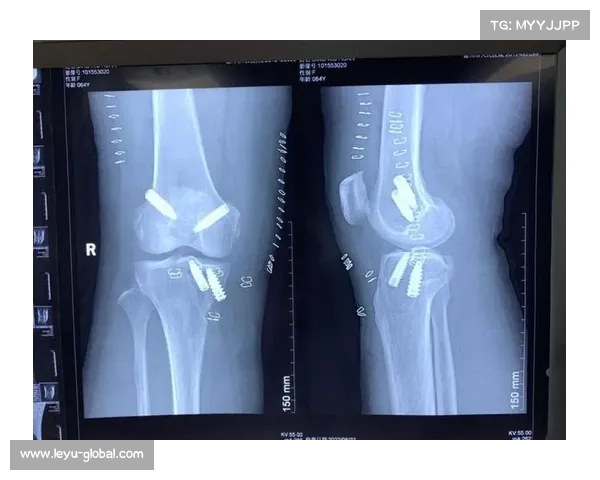

在手术前,刘斌进行了详细的体检和影像学检查,包括X光、MRI等,以确认膝关节的损伤程度。在充分评估了膝关节的状况之后,医生为刘斌制定了详细的手术方案。手术过程需要全身麻醉,以确保患者在手术期间完全无痛,并且避免剧烈的运动导致术中意外。

手术过程中,医生会在膝关节外侧进行小切口,取出患者的股四头肌腱,并将其制备成符合前交叉韧带的长度和强度要求的移植物。接着,医生通过关节镜技术,清除损伤的前交叉韧带残端,并通过专业工具在股骨和胫骨上打孔,以便将新的韧带移植物固定在合适的位置。

固定移植物时,医生会使用钉子、螺钉或其他固定装置,确保移植物牢固地固定在关节内。手术过程中,整个操作的精度和细致度至关重要,任何细小的偏差都可能影响膝关节的稳定性,进而影响患者的恢复效果。